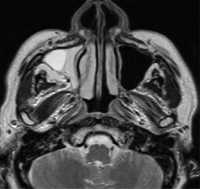

MRI

右上顎洞の炎症所見

積極的に腫瘍性病変を示す所見なし

高タンパク内容を反映する信号強度

MRIT1強調横断像

MRIT2強調横断像